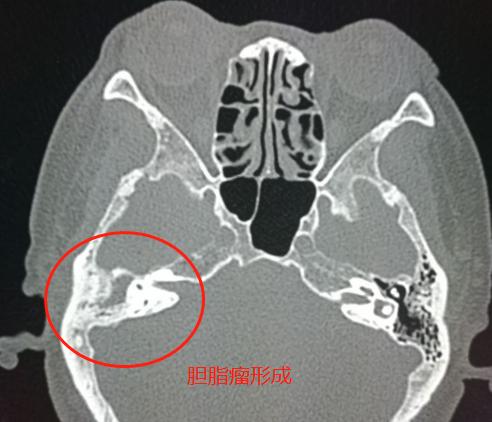

3.中耳炎继续进展,乳突周围骨质破坏,形成胆脂瘤(恶臭)——

局部骨质破坏,形成具有恶臭味的胆脂瘤

慢性中耳乳突炎多年,反复发作,发生了胆脂瘤,中耳结构破坏,听力明显下降。

到这个时候就只能手术治疗了。

4.胆脂瘤形成,手术后图片——